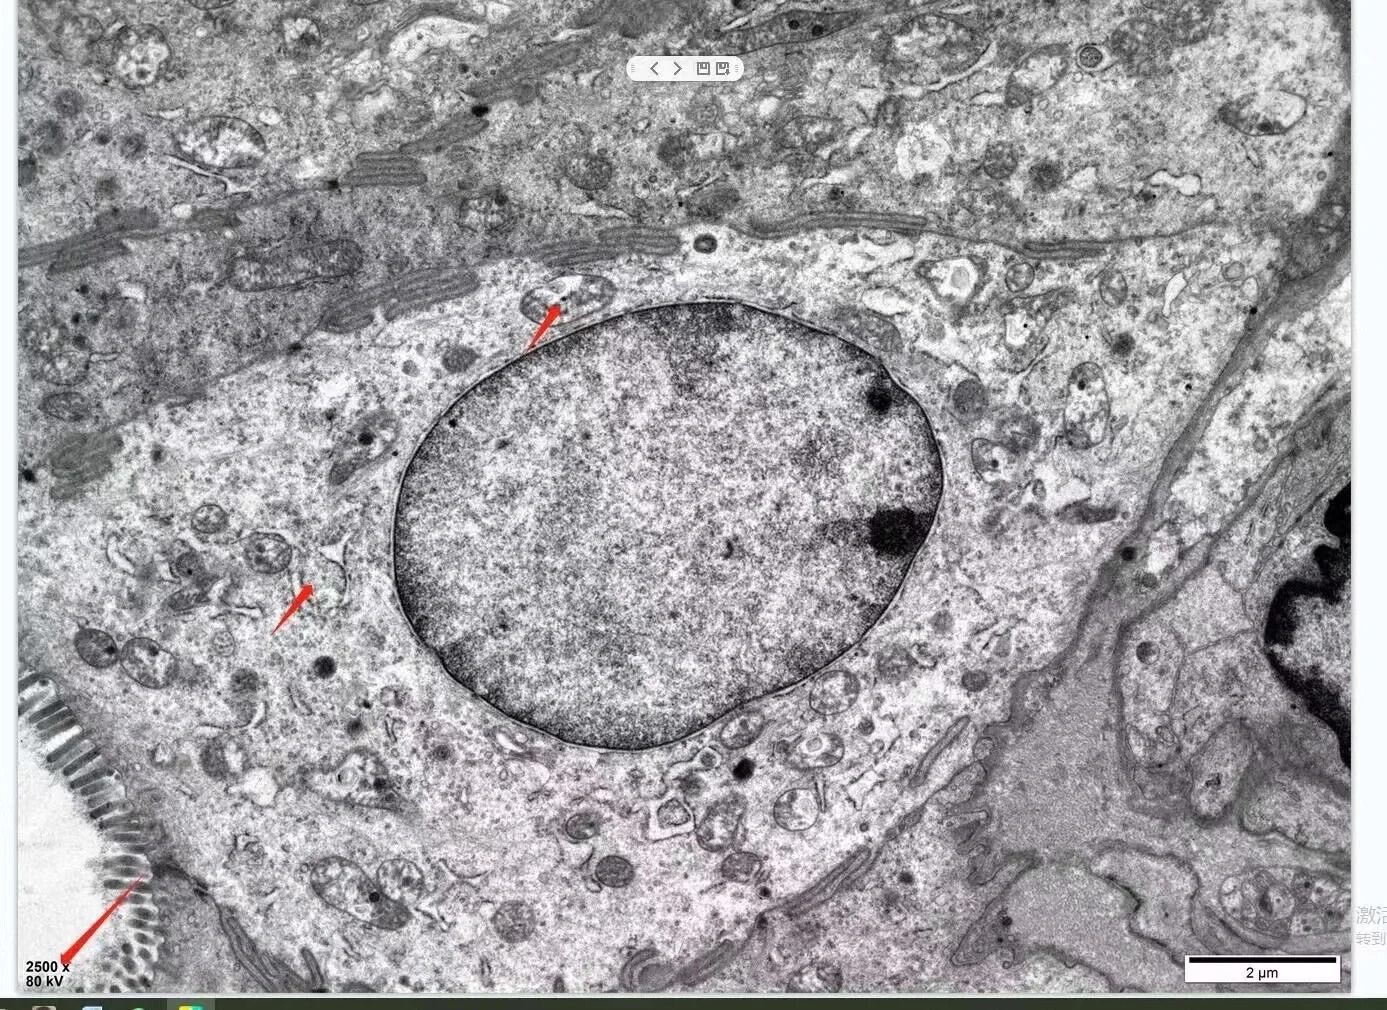

細(xì)胞結(jié)構(gòu)

在獲取實驗數(shù)據(jù)時,我們可以選擇拍攝不同放大倍率的圖像,以觀察樣品的形貌和內(nèi)部結(jié)構(gòu)。此外,通過調(diào)整TEM的衍射鏡,我們還可以獲得樣品的電子衍射圖,用于分析樣品的晶體結(jié)構(gòu)和晶相組成。